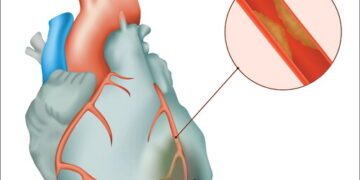

Read moreঅধ্যাপক ডা. এসএম মোস্তফা জামান বর্তমান সময়ে সবচেয়ে আতঙ্কের রোগ হচ্ছে হার্টঅ্যাটাক। সুস্থ-সবল মানুষ মুহূর্তেই বুকের ব্যথায় কাতর হয়ে পড়ে।...

Read moreহার্টবিট ডেস্ক হৃদযন্ত্রের ক্রিয়া বন্ধ হয়ে প্রায় ৮০ শতাংশ মানুষের মৃত্যু হয়। কিন্তু কেউ এ ধরনের রোগে আক্রান্ত আছে কিনা...

Read moreহার্টবিট ডেস্ক হার্ট আমাদের দেহের এমন একটি অংশ যা ছাড়া বেঁচে থাকা অসম্ভব। আর কোনো ভাবে যদি এর ক্ষতি হয়...